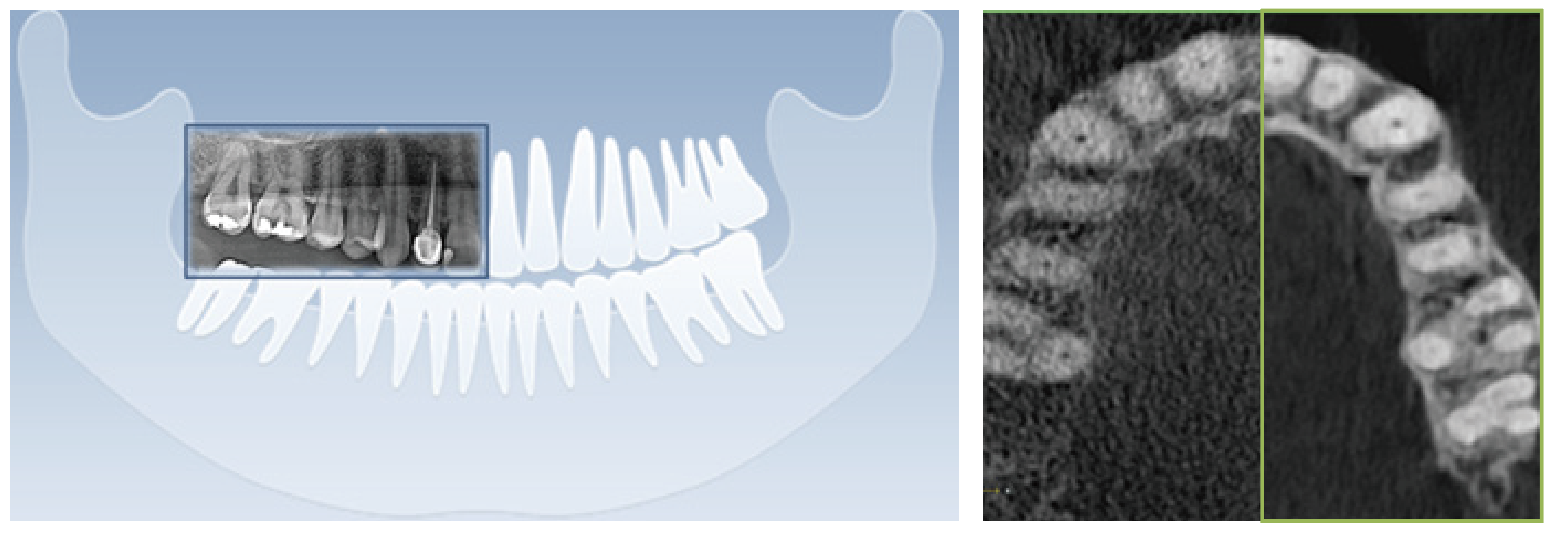

清晰的全景影像

通過多層技術,可以拍攝多張圖像,每張圖像被進一步分割。系統會自動選擇最佳焦點將其整合成一個優化的全景圖像。

前牙部畸變縮小,即使不單獨拍攝小牙片,也能準確診斷。清晰度可準確識別種植體螺紋和內部,確保連接程度和斷裂程度。